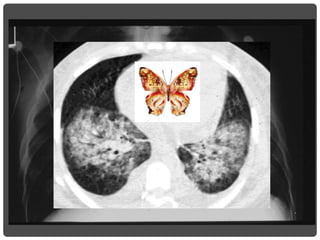

3. CAVIDADES

Opacidad periférica con centro radiolúcido.

Puede ser única o cavidades múltiples,

dependiendo de la etiología.

Causas

• Infecciosas: absceso, TBC, micosis, parásitos

(quiste hidatídico).

• No infecciosas: Sarcoidosis, G. de Wegener,

AR, quiste broncogénico, bronquiectasias

quísticas.

• Neoplasias: tumores abscedados.

CAVIDADES